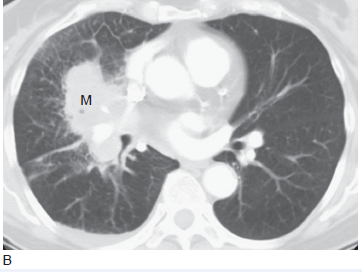

肺癌的影像学表现

肺癌的影像学表现,肺癌的ct影像学表现

肺癌的ct影像学表现

肺癌ct图片影像学

肺癌ct

肺癌ct图片